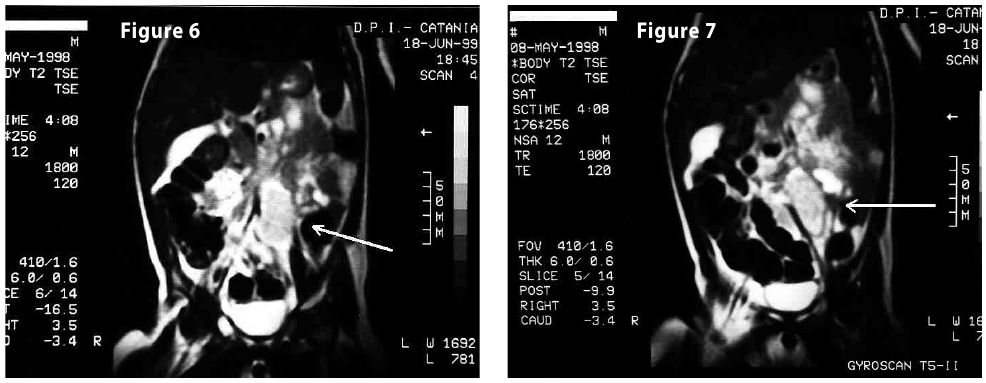

Figure6-7

Figure8-9